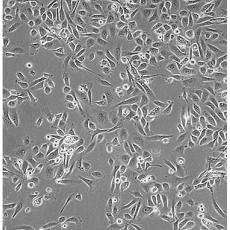

PC-3(PC 3)

中文名稱 人前列腺癌細胞

組織來源 前列腺癌;骨髓轉移;男性

細胞種屬 Homo sapiens, human

生長特性 adherent

培養(yǎng)基 Ham's F-12K+10% FBS+1% P/S

形態(tài)特征 epithelial

傳代方法 1:3-1:6

培養(yǎng)條件 Atmosphere: Air, 95%; CO2, 5%。Temperature: 37℃

細胞描述 PC-3源于一位62歲白人男性IV級前列腺腺癌患者的骨轉移灶;有低水平的酸性磷酸酶活性和5-α-睪酮還原酶活性。